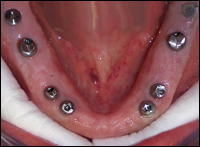

Fig 4 & 5: The upper and lower arches received 8 dental implants each . Using Simplant and SurgiGuide technology, the implants were placed without any incisions, bleeding or stitches. These photos were taken the same day the implants were placed.